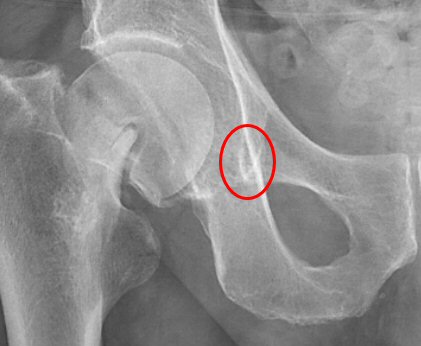

- Lägg horisontell referenslinje mellan nederkant på teardrops, tuber ischiadicum eller neder- eller överkant foramen obturatoria.

Teardrop är konturen av nedre kanten på mediala väggen i acetabulum, markerat på bilden ovan. Dessa visualiseras inte alltid lika tydligt som i detta exempel.

Referenslinje lagd med teardrops nedre kanter som referenspunkter